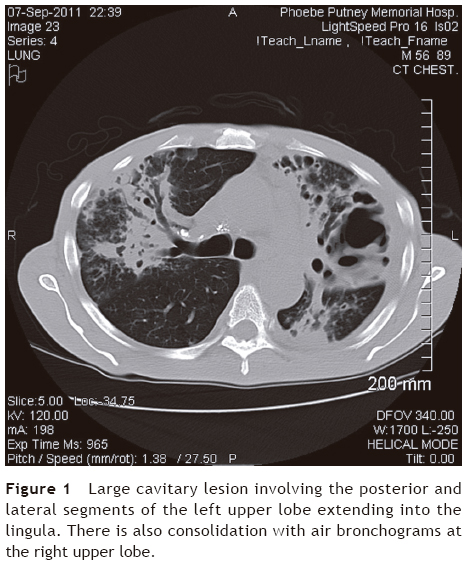

We conducted a descriptive, observational and retrospective review of clinical cases of suspected pulmonary TB (TB Class V as per the International Union Against Tuberculosis and Lung Disease) during a 2-year period (September 2011 to September 2013) in two large districts in southwest Georgia (U.S.) to identify the number of those infected with bacterial pathogens in the group of Actinomycetales. We were particularly interested in identifying those cases where Tsukamurella spp. or Rhodococcus spp. were isolated during the clinical workup of cases of presumed pulmonary TB. We defined cases according to their clinical presentation (fever, night sweats, productive cough for many weeks, malaise, weight loss, and hemoptysis) and chest radiograph or CT scan of the chest with findings compatible with pulmonary TB (cavitary lesions, endobronchial spread of pneumonia, or upper lobe pneumonias) (Fig. 1).